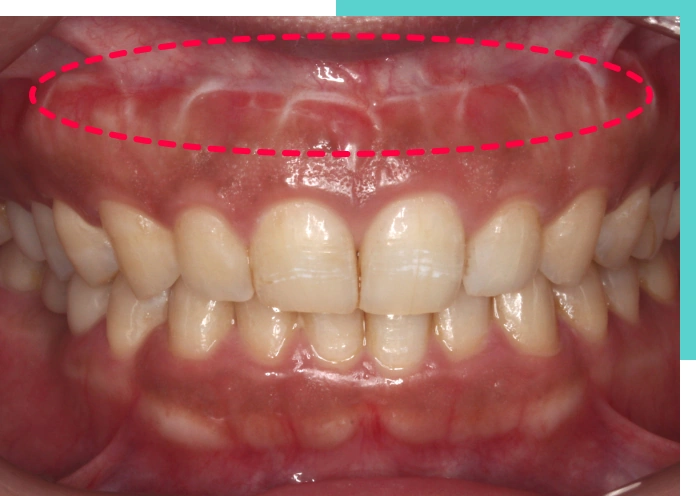

唇の位置や形の問題

施術前、施術後写真

くちびるや口元周りの筋肉が強い場合、笑う時にくちびるが上がりすぎてしまうため、ガミースマイルになってしまいます。

※上の写真は他院での口唇縫合術後の短期間での後戻り症例写真です。

くちびるや口元周りの筋肉が強く、笑うときにくちびるが上がりすぎる状態を改善する方法の1つに、上口唇の裏側の粘膜を切除して上前歯の歯ぐき(歯肉)と縫い合わせる口唇縫合術(粘膜切除術、リップリポジショニング)という方法もあります。

軟組織(やわらかい歯肉)を縫合する処置なのですが、手術後に短期間で後戻りしやすいという大きな欠点があります。